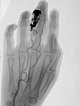

After incomplete transarterial embolization of the AVM 2 years ago, a recurrence of the AVM has appeared. During previous embolization only a part of the AVM was occluded, which actually increases the risk of recurrence. The old radiopaque embolic agent of the previous embolization can be seen centrally in the nidus.

The nidus of the AVM in a magnified target image of the D III in digital subtraction angiography shows significant increase in size compared to the old angiographies (not shown). DSA images after transarterial antegrade puncture of the brachial artery with hypervascularized AVM of the middle and distal phalanx.

Angiographic control of the right hand with catheter injection from transarterially via the ulnar artery. Complete devascularization of the AVM nidus. No fast-flow shunts can be angiographically detected. The treated AVM with occluded nidus is thus resectable.

Fluoroscopic view of the cast after successful nidus embolization of the AVM. To improve the overview for surgical planning, this image is also shown without subtraction with visible bone.